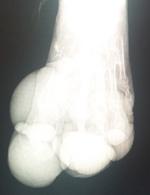

12月に突然現れた怪我猫ちゃん

「おちいちゃん」です。

【12月保護猫近況・おちいちゃん】

前足の違和感は「遺伝性骨形成異常症」です。

違和感の足は『遺伝性骨形成異常症』で

傷になった箇所は怪我をしたと言うよりも

急な野外でアクシデントなどの衝撃や、酷使でも痛みが伴い

頻繫に舌で舐めたので化膿していたのではないかと診断です。

(当方に至るまでの経緯が不明ですので状態での判断です)

野外生活はかなりのリスクで完治は出来ない困難な病。

かかりつけ獣医とセカンドオピニオンは

双方ベテランの獣医で二人が同様の見解でした。